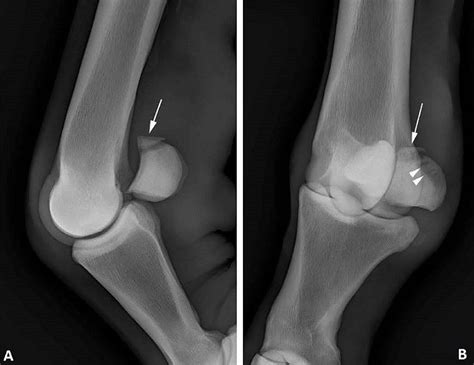

• X-Rays: X-ray images to visualize the bones and identify any fractures.

• MRI or CT Scan: Advanced imaging techniques to provide a more detailed view of the sesamoid bones and surrounding tissues.